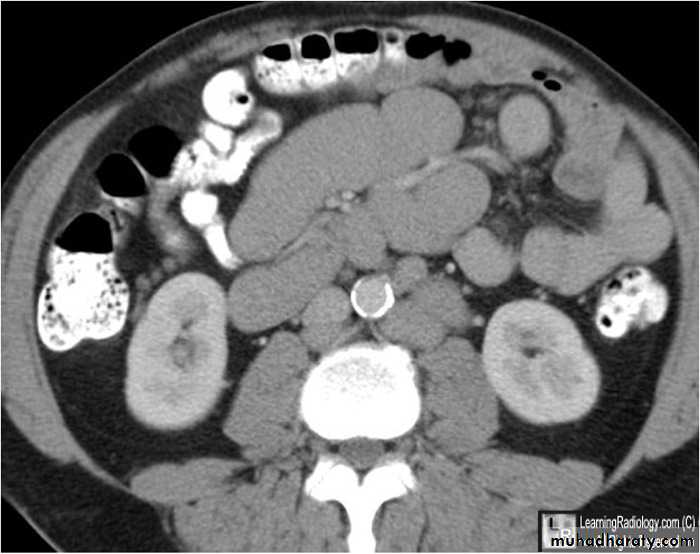

Lymphadenopathy